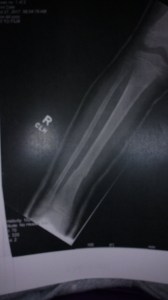

We have hit the three-month milestone since Scottโs back surgery. To recap, he fell ten feet from our roof to the concrete while cleaning the gutters. He broke two vertebrae necessitating an urgent surgery followed by a ten-day stay in the hospital.ย ย We anticipate that the doctor will soon โreleaseโ him to โbend, life and twistโ or BLT as they said. I joked that when this happens I am going to throw a bunch of stuff on the floor and watch him pick it up!